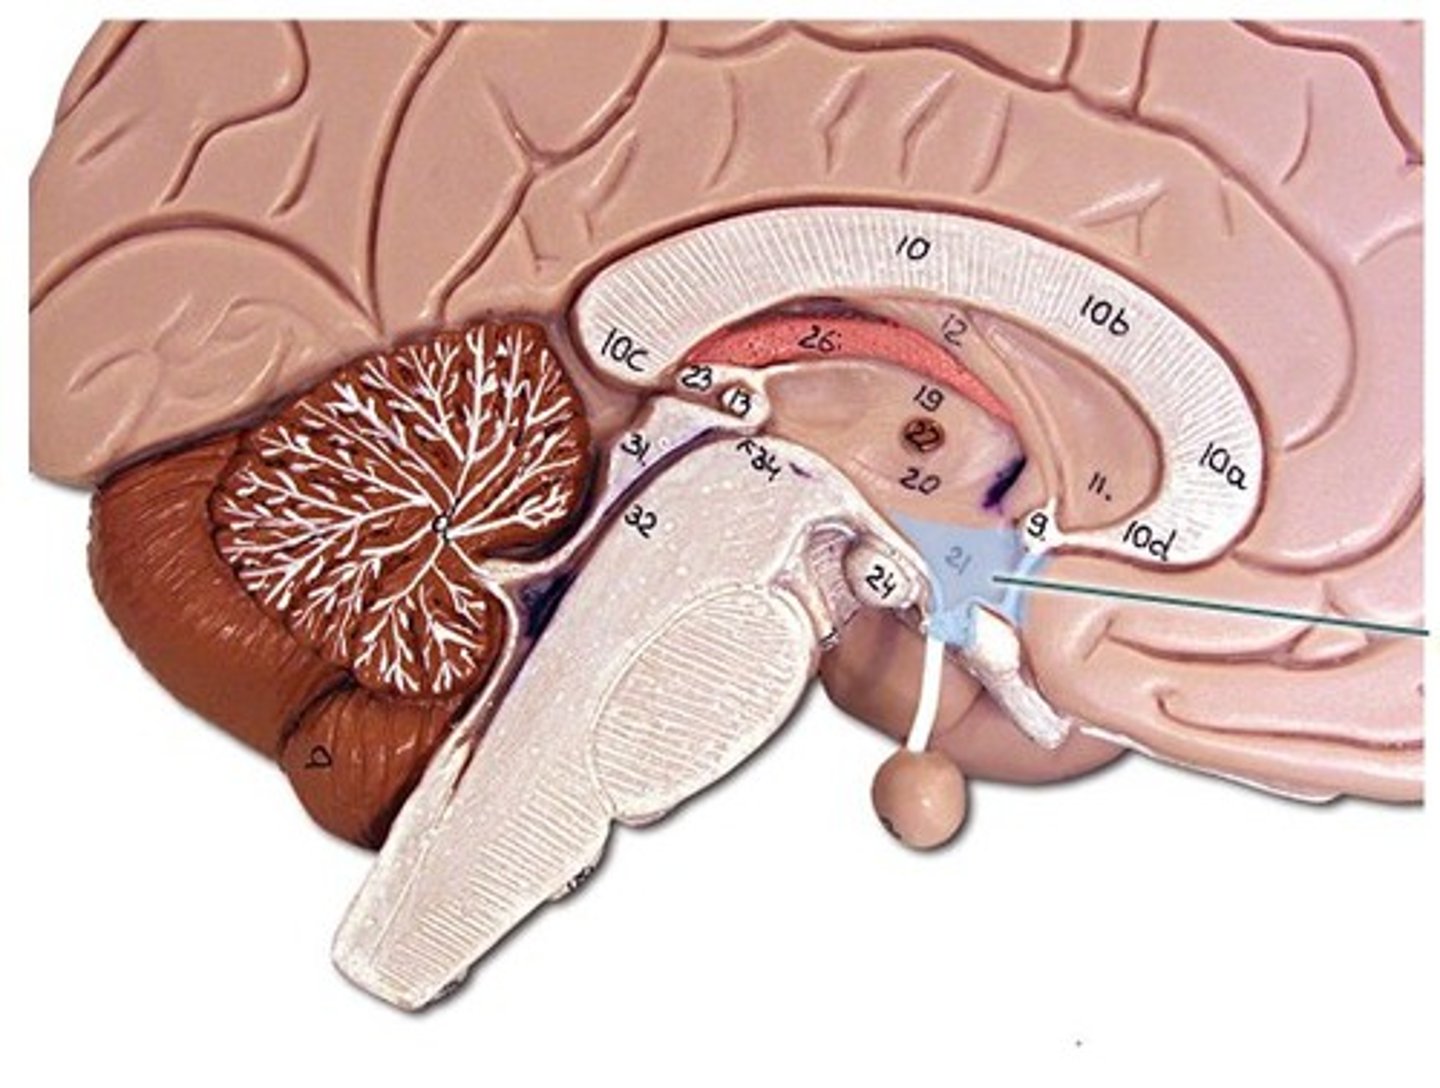

limbic system

a doughnut-shaped system of neural structures at the border of the brainstem and cerebral hemispheres; associated with emotions such as fear and aggression and drives such as those for food and sex. Includes the hippocampus, amygdala, and hypothalamus.

amygdala

two almond-shaped neural clusters that are components of the limbic system and are linked to emotion- anger, aggression, & fear

hypothalamus

a neural structure lying below the thalamus; directs eating, drinking, body temperature; helps govern the endocrine system via the pituitary gland, and is linked to emotion. Pleasure center and Reward center of the brain